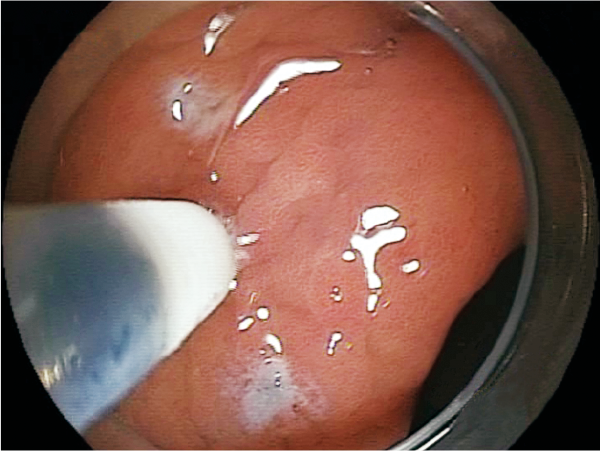

Clinical Image :Marking

Clinical Image :Water jet

Clinical Image :Mucosal Injection

Clinical Image :Submucosal dissection

Clinical Image :Submocosal injection

Clinical Image :Coagulation